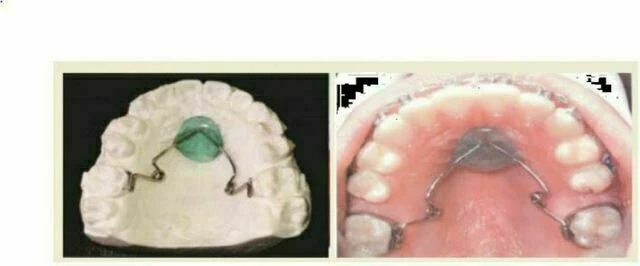

3. Viaro Nance

Kiểu neo chặn trung bình này là một biến thể của Nút Nance, người tạo ra nó là bác sĩ Victor Avalos Rodriguez, bác sĩ chỉnh nha tốt nghiệp Centro de Estudios de Ortodoncia del Bajio (CEOB) ở Irapuato, Guanajuato, Mexico. Nó được làm bằng dây TMA (titanium molybdenum alloy) và có 2 vòng xoắn phải được kích hoạt mỗi tháng 1 lần để di xa răng cối. Dây này phải được luồn vào ống mặt lưỡi hàn trên khâu răng cối hàm trên để tạo thành một neo chặn tháo lắp.

a. Ưu điểm

b. Nhược điểm

c. Lời khuyên